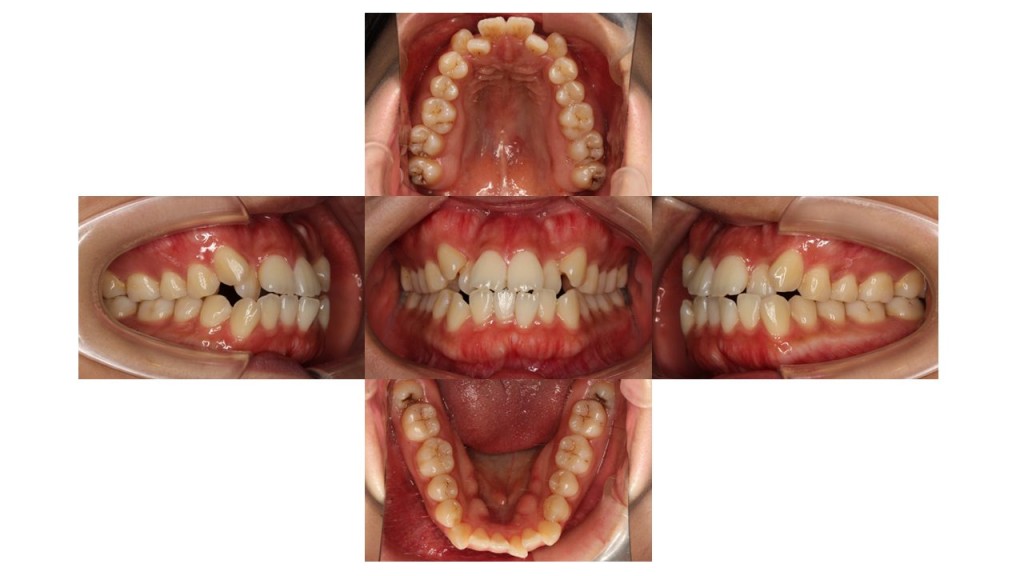

初診時の口腔内の状態です。

八重歯と前歯の凸凹にお悩みでご来院されました。